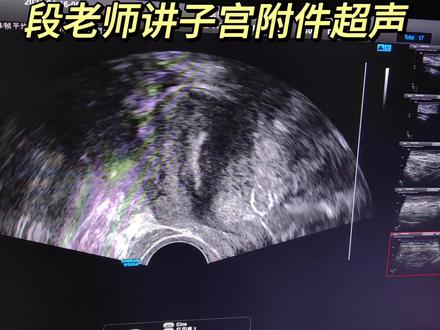

子宫前倾,然后正常子宫是应该往前歪的,这是膀胱吗?因为病人因为做阴超需要排空膀胱,现在这是一个膀胱壁,他里边一点尿也没有。嗯,然后这是一个前卫的子宫。嗯,他做剖腹产,这是那个剖宫产的切口,在这个地方明显看见基层连续不太完整。 然后正常子宫前面应该是往前,在他可能因为做剖腹产子宫有点往上掉。嗯嗯,可能有点粘连,这是宫颈,宫颈已经被拉的很长了,可以看着。嗯,正常,这是做剖腹产的原因。 然后我们看一下右侧的卵巢,这是这看见打横切,他是一个卡血管,一般卵巢就在卡血管的内侧,可以看光这一个切面就能到十二个以上。这是一个很典型的多囊,这是卵巢,一看也挺大的。我们再看对侧,这 是恰血管吗?恰血管的内侧也是多呢,卵泡也挺多的。盆腔没有很明显的积液啊,有一丢丢,别的没有事。